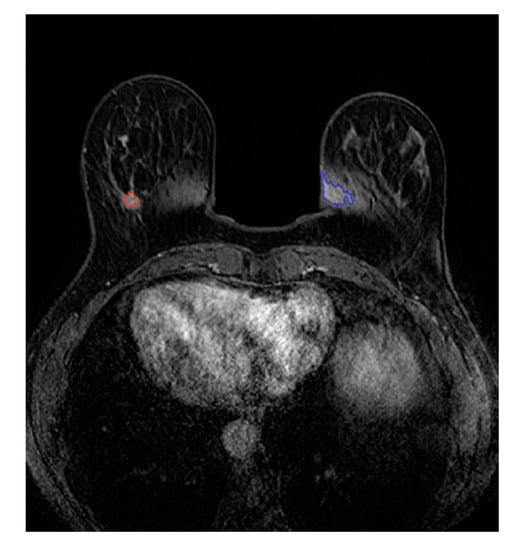

2.3. FP ROI Rejection through Binary Classification

2.4. Tumor Characterization by Radiomics Signature